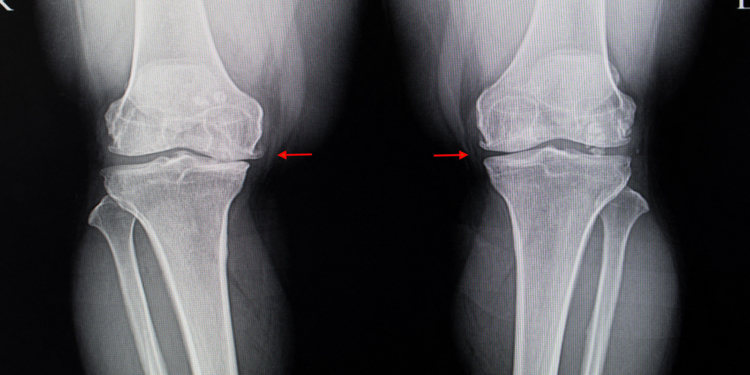

(MedPage Today) — Hopes that the plant extract known as diacerein could relieve pain and disability from osteoarthritis (OA) of the knee now seem forlorn in the wake of an Australian trial that failed to find any benefit.

Among 262 patients with…